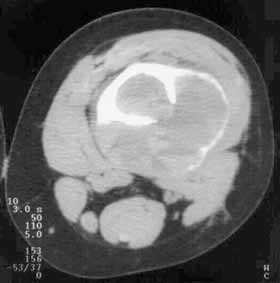

Рис. 3. Аневризматическая костная киста бедренной кости. (Слева) Рентгенограмма в боковой проекции. (Справа) Компьютерная томограмма.